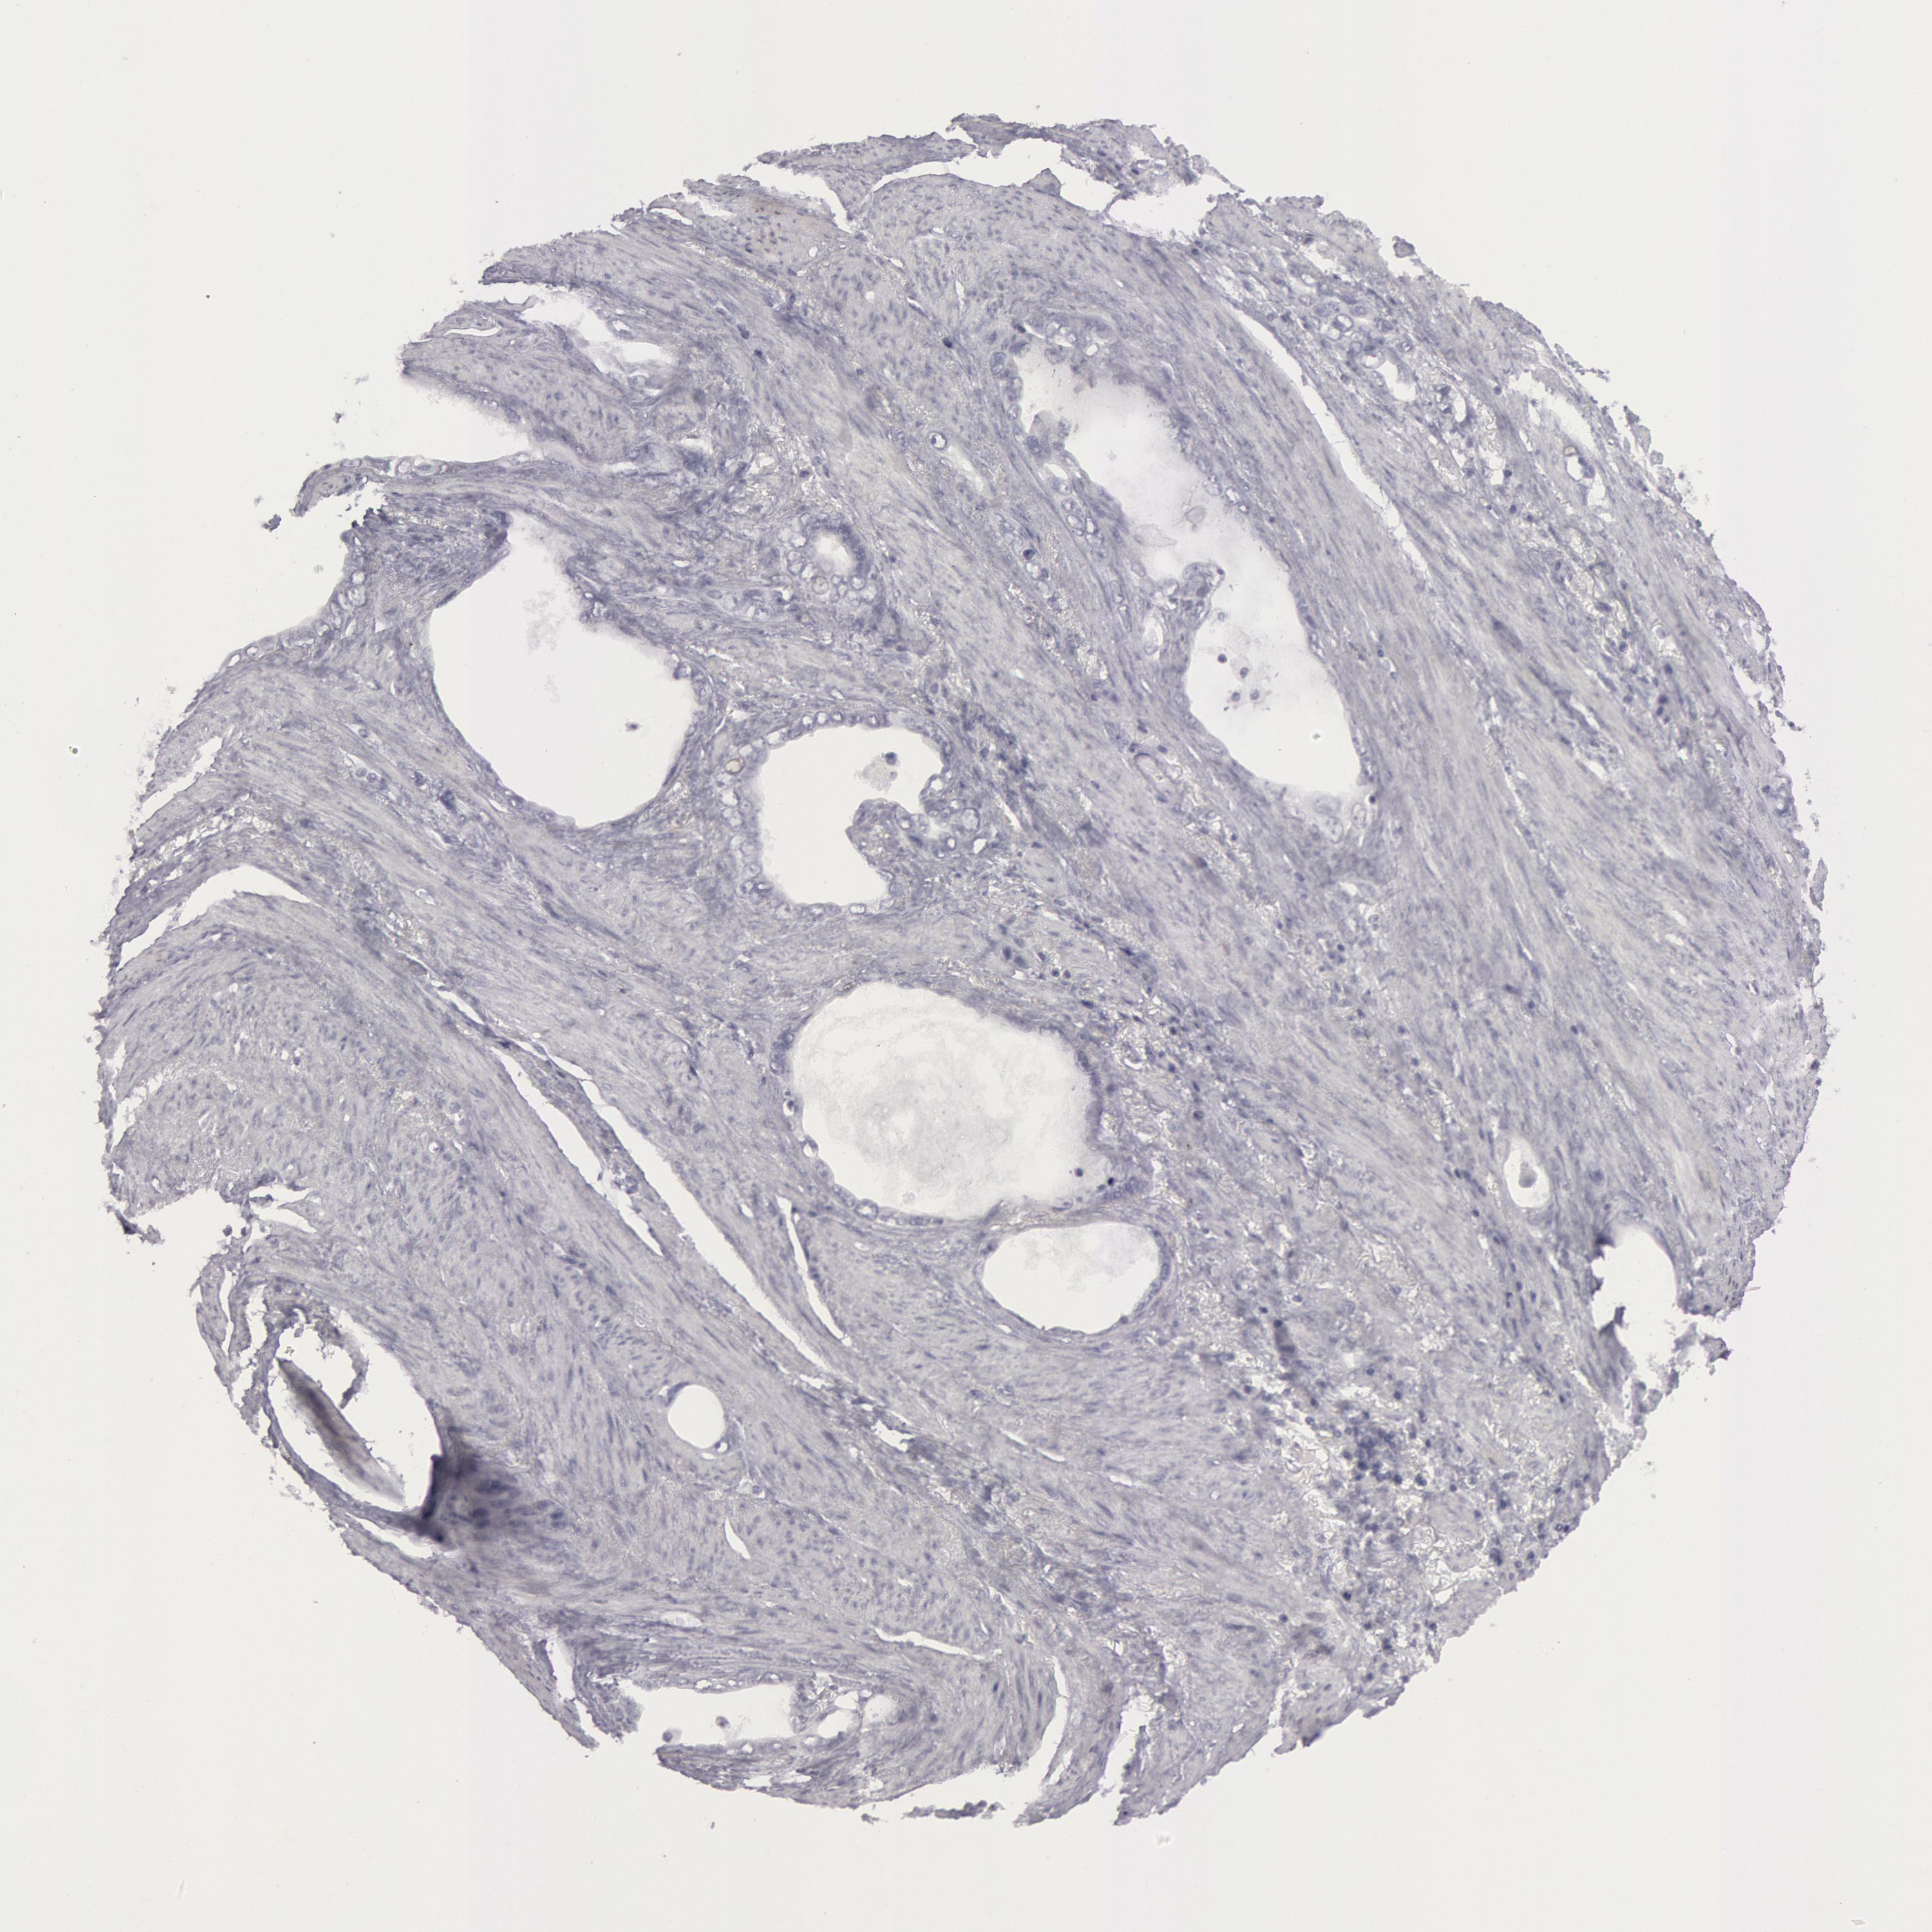

STOMACH CANCER - Protein expressioni

A mouse-over function shows sample information and annotation data. Click on an image to view it in a full screen mode. Samples can be filtered based on level of antibody staining by selecting one or several of the following categories: high, medium, low and not detected. The assay and annotation is described here.

Note that samples used for immunohistochemistry by the Human Protein Atlas do not correspond to samples in the TCGA dataset.

Antibody stainingi

Antibody staining in the annotated cell types in the current human tissue is reported as not detected, low, medium, or high, based on conventional immunohistochemistry profiling in selected tissues. This score is based on the combination of the staining intensity and fraction of stained cells.

Each image is clickable and will lead to virtual microscopy that enables deeper exploration of all samples and also displays staining intensity scores, fraction scores and subcellular localization as well as patient and tissue information for each sample.

Antibody CAB000136

Staining

High

Medium

Low

Not detected

Intensity

Strong

Moderate

Weak

Negative

Quantity

>75%

75%-25%

<25%

None

Location

Nuclear

Cytoplasmic/membranous

Cytoplasmic/membranous,nuclear

Adenocarcinoma, NOS